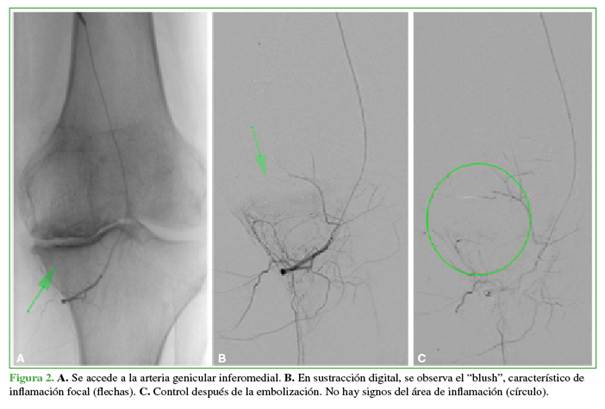

Se le propone la embolización arterial selectiva (Figura 2).

El paciente refiere franco alivio sintomático tras la embolización (Figura 3).

La técnica consiste en la embolización superselectiva de ramas arteriales geniculares que irrigan áreas de neoangiogénesis sinovial, buscando una reducción controlada —aunque no la oclusión completa— del flujo hacia los vasos patológicos, con el objetivo de disminuir la inflamación y el dolor, minimizando, a su vez, el riesgo de isquemia en tejidos vecinos (Figura 4).13